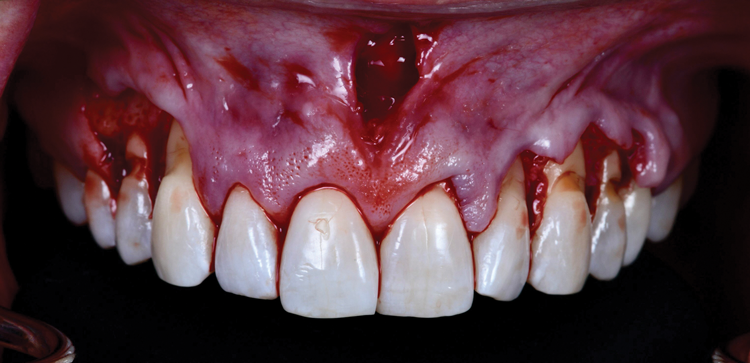

In order to take advantage of the benefits of the above-mentioned flap designs while minimizing the limitations, the frenectomy anterior tunnel sulcular access channel approach combines envelope flaps with a vestibular access tunnel by incorporating the maxillary midline frenum (Figure 4). This technique, which can be especially helpful for treating generalized recession affecting the upper anterior teeth, is demonstrated in the following case report.

Given the importance of anterior esthetics as well as the clinical need for root access to address the NCCLs, no single flap design would suffice to solve the dilemma of esthetics versus root access in this case. And the presence of the patient's prominent midline frenum only added to the challenge of managing flap tension. Therefore, the proposed solution was a frenectomy anterior tunnel sulcular access channel approach. In this approach, a frenectomy procedure was performed to create a vestibular access point, followed by the creation of envelope flaps over the posterior teeth with gingival recession. This approach accomplished three goals: safe tunneling of the mucoperiosteal flap over the incisors without the need for papillae reflection, simple flap release over the teeth with gingival recession to provide space for the soft-tissue graft, and establishment of an easy access point to position the graft over the roots (Figure 7). Keeping the papillae between the incisors intact solved the esthetic concerns of the case, and the envelope flaps over the posterior teeth would permit the NCCLs to be reduced and smoothed with rotary instruments to provide a flat or concave surface for the graft material,10 which is very difficult or impossible with a tunnel flap. It is convenient that most NCCLs occur on posterior teeth5 because that allows an envelope flap for sulcular access and visualization to be incorporated with minimal effect on the esthetics. By combining a frenectomy with posterior envelope flaps for sulcular access, the frenectomy anterior tunnel sulcular access channel approach indeed creates a "channel" so that the soft-tissue graft can be placed over the roots from either direction and direct visual confirmation is possible to ensure proper placement (eg, no folding of the material, proper root coverage). If this approach was not used, one could imagine the challenges of properly placing the graft within a tunnel flap or through a single vestibular incision (Figure 8).

Mobility of the anterior tunnel portion of the flap was achieved by scoring the periosteum through the frenectomy incision. The flap release in the posterior envelope sections of the flap was achieved through the coronal (ie, sulcular) area. These steps were important to both create space for the graft material and ensure complete passive closure over the graft without excess flap tension. After this, the NCCLs were smoothed with rotary instruments to provide smooth, flat (or concave) surfaces. A soft-tissue allograft was then introduced through the frenectomy incision, passed through the "channel" over the incisors, and then retrieved through the envelope portion of the flap on both the left and right sides. After the graft was sutured to the CEJs with independent sling sutures using 4-0 chromic gut sutures (as can be seen in Figure 4), the overlying flap was coronally advanced over the allograft and sutured with independent sling sutures using 4-0 polypropylene sutures, and the frenum was closed with interrupted sutures also using 4-0 polypropylene sutures (Figure 9). To confirm passive closure of the flap, the patient's lips and cheeks were then manipulated in various directions. Care was taken to be sure that no allograft material was exposed.

(4.) Example of the frenectomy anterior tunnel sulcular access channel approach, which combines envelope flaps with a vestibular access tunnel by incorporating the maxillary midline frenum.

Figure 4